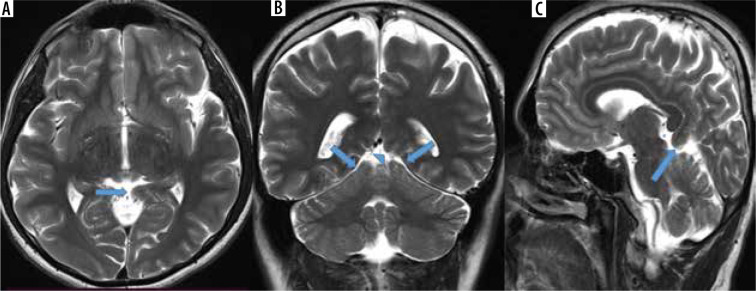

Purpose: The tent shape of the tentorium cerebelli helps preserve brain anatomy by providing cerebellum protection against pressure caused by the brain's gravity effect. In the absence of this support structure of the tentorium, herniation occurs in the brain. Isolated tentorial hypoplasia (TH) is extremely rare. In this study, we aimed to calculate the prevalence of this entity, which is reported to be rare in the literature.

Material and methods: Magnetic resonance imaging (MRI) images of 5163 patients who applied to the training and research hospital for various reasons between 1 September 2020, and 31 August 2021, who underwent brain MRI, were reviewed retrospectively.

Results: The prevalence of TH among patients screened during a period of one year was calculated as 2.22%. Of these, 76.59% were female (n = 72) and 23.41% were male (n = 22). The rates of presentation of complaints among TH patients were 60.63% headache, 17.02% vertigo, 4.25% seizures, 3.19% tremor, 3.19% syncope, 7.44% forgetfulness, and 2.12% visual impairment. Five patients (11.76%) were admitted for metastasis investigation due to their primary malignancy; they did not have any complaints. Localization of TH: 18.08% (n = 17) were observed on the right side, 28.72% (n = 27) on the left side, and 53.19% (n = 50) on the bilateral tentorium leaf.

Conclusions: Being aware of TH during brain MRI evaluation will help prevent possible misdiagnoses. We hope that this study with a large number of patients will increase awareness about TH, because there are no studies other than cadaver studies and a few case reports.